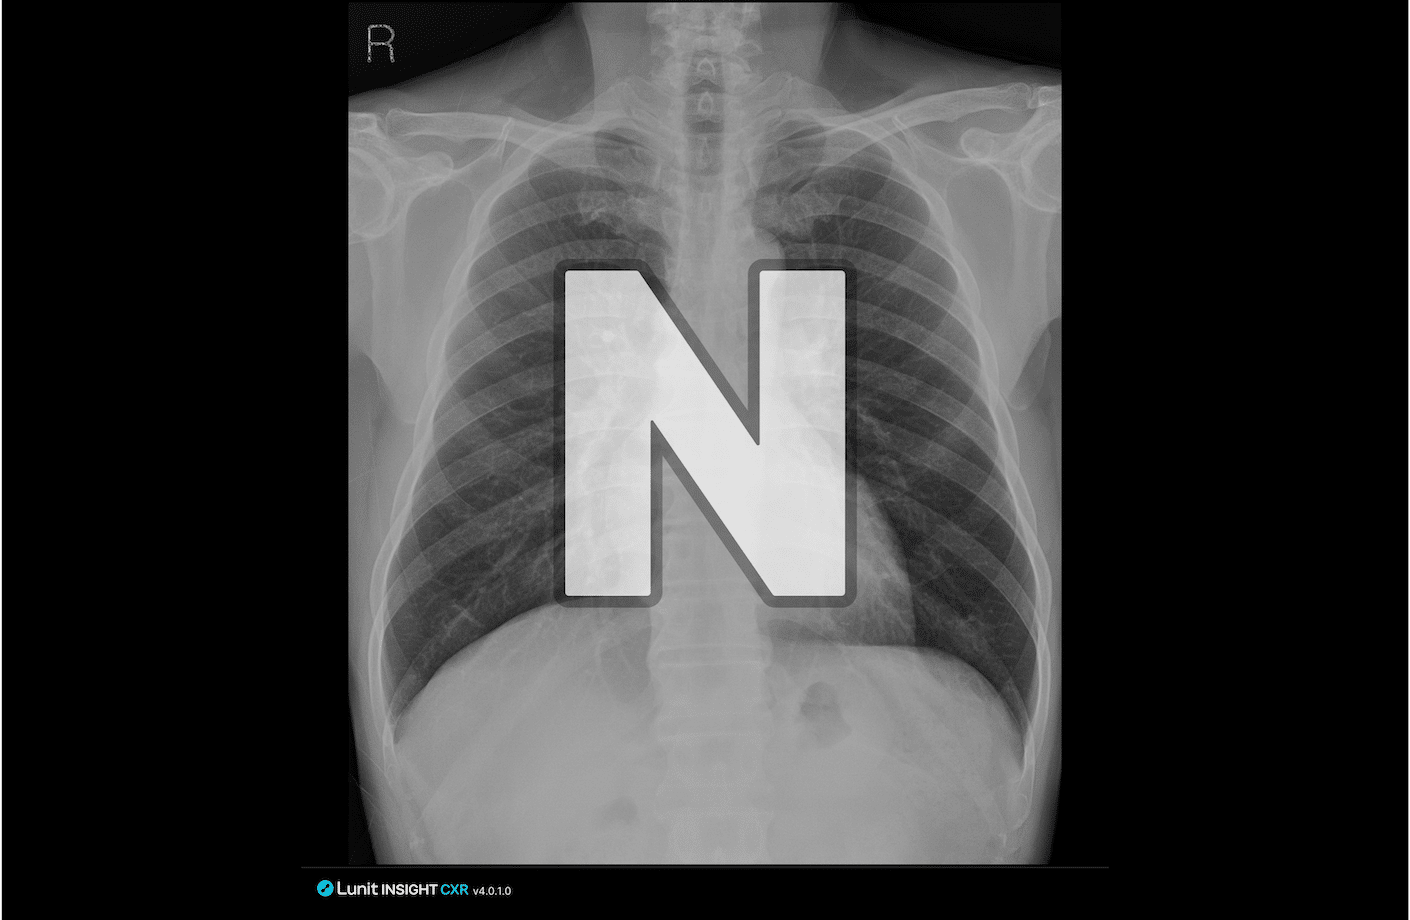

루닛 인사이트 CXR4는 흉부 엑스레이 판독을 지원하는 AI입니다. PACS등 기존 워크플로우에 자연스럽게 통합되어, 복잡한 흉부 질환을 식별할 수 있도록 보조합니다.

특히 루닛의 Dual AI Engine(Abnormality AI Engine, Normal Flagging AI Engine)을 기반으로, 정상 소견을 분류하고 의심 소견이 있는 영상을 표시해 판독 업무 효율 향상¹에 도움을 줄 수 있습니다.